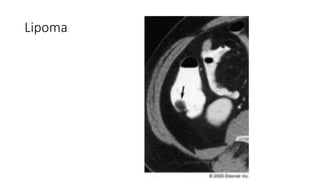

Tumores Benignos del Colon

• Mas frecunte el adenoma seguido por el lipoma

• Lipomas generalmente asintomáticos. Pueden causar intususcepción

o ulceración y necrosis

• Colonografia por TC: se localizan lesiones en submucosa con características de

grasa.

Lipoma

Tumores Benignos delColon • Mas frecunte el adenoma seguido por el lipoma • Lipomas generalmente asintomáticos. Pueden causar intususcepción o ulceración y necrosis • Colonografia por TC: se localizan lesiones en submucosa con características de grasa.